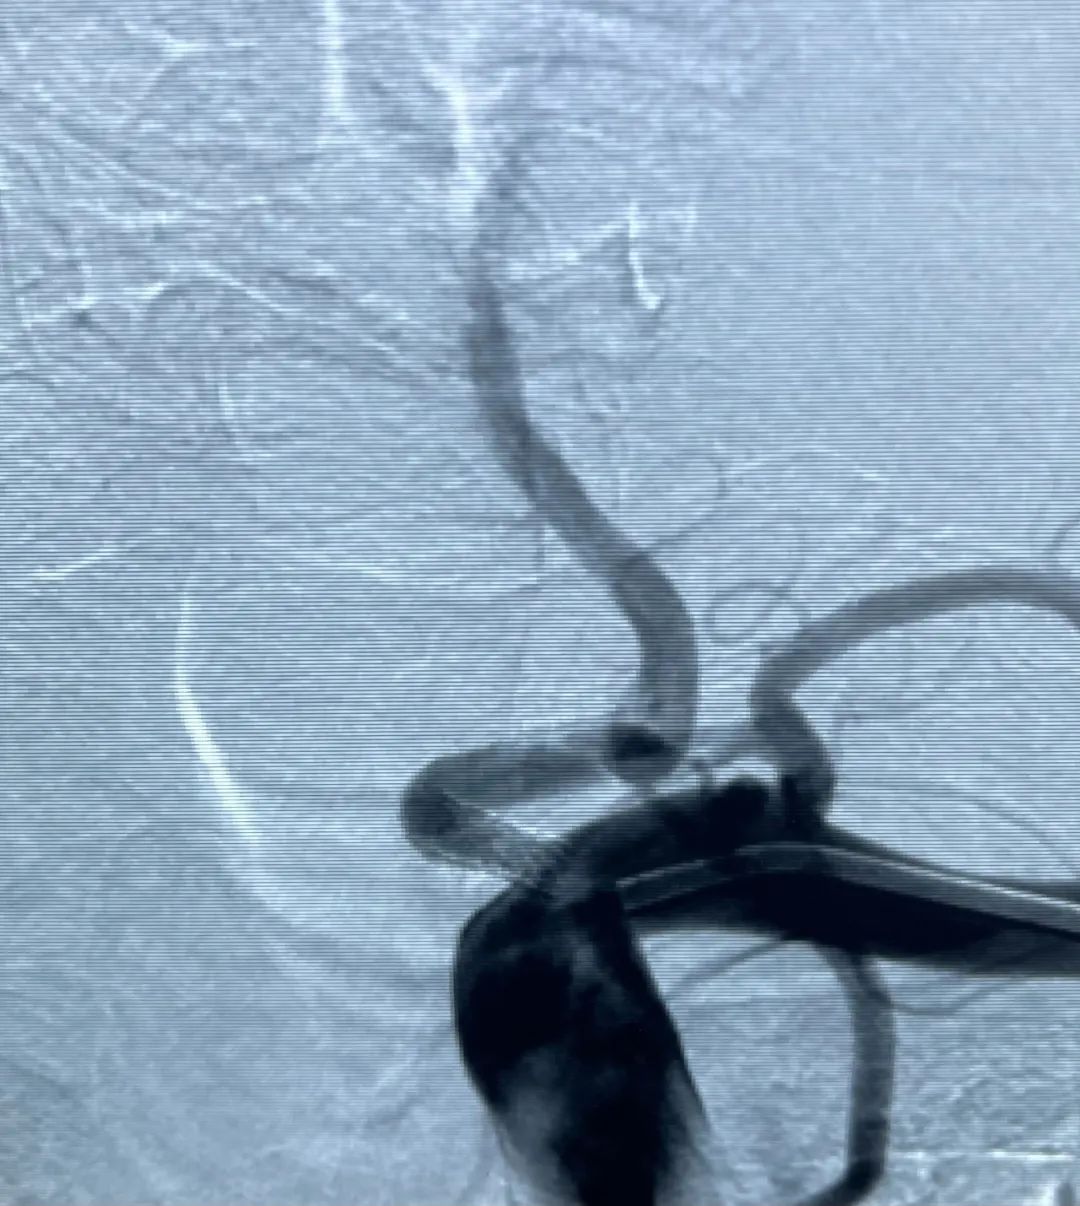

▲手术后

手术治疗:对于严重的椎动脉狭窄或药物治疗无效的患者,可以考虑手术治疗。手术治疗的方法包括血管内支架置入术、内膜剥脱等。